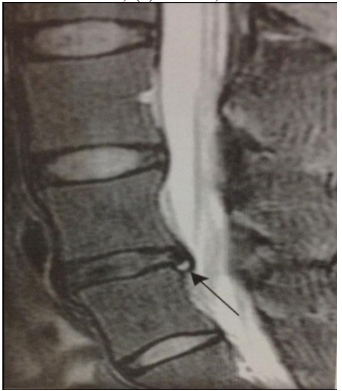

Na imagem a seguir, apresentada no manuscrito de Vieira, Predes e Pereira. Rev JRD de Estudos Acadêmicos. 2021;4(8):4667046, a seta indica: